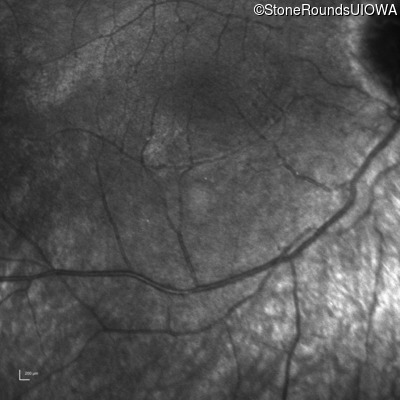

Infrared Fundus Photograph - Right -

No Light Perception

Exemplar

Expanded OCT Stack

×